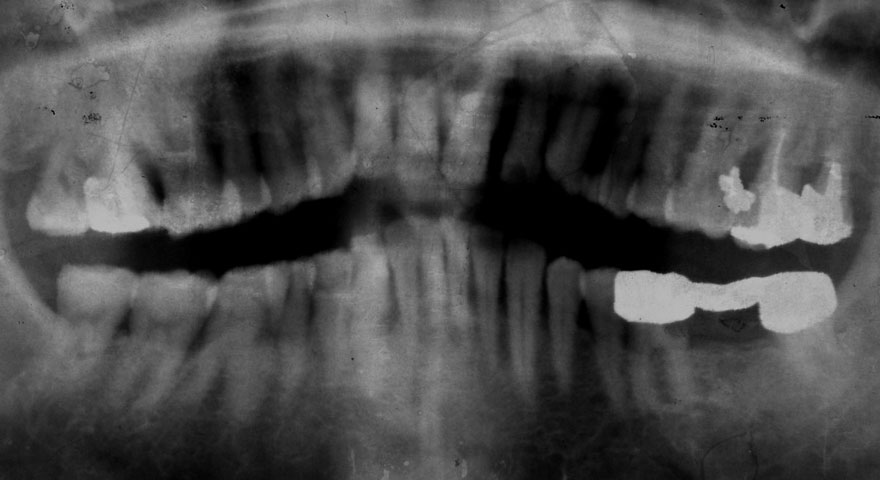

初診時 62歳 女性 平均歯槽骨喪失量:3.98mm

22年後 86歳

平均歯槽骨喪失量:4.03mm

22年間喪失量:-0.05mm

年間喪失速度:-0.002mm

(ケア頻度:1.12ヵ月ごと)